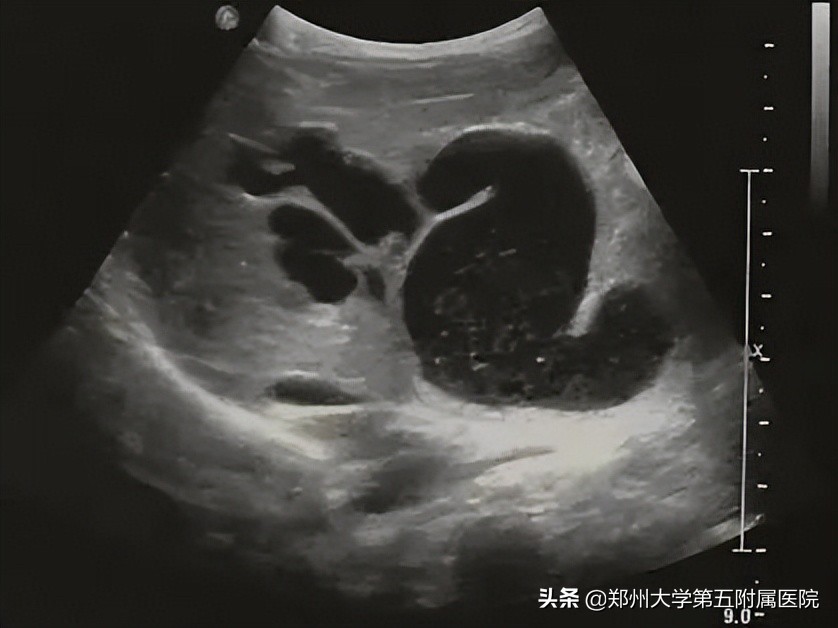

胆道闭锁 患儿生后即出现黄疸、进行性加重、皮肤巩膜黄染、面色暗黄、大便淡黄色或白色陶土样等症状。由于新生儿胆总管纤细难以观察,因此通过以下胆囊形态变化判断是否胆道梗阻: 胆囊大小正常但形态僵硬 (图2),边缘不光整,长度可达2-3cm,内径大于0.4cm,可有小的憩室样结构形成; 小胆囊 ,长度小于1-1.5cm,内径0.2cm,充盈差; 胆囊小而且无充盈,仅可见胆囊痕迹,喂奶后无变化 ;以上三种胆囊均可合并有 胆总管区囊肿,可与胆囊管及胆囊相通 ,但 与肝左、右管不相通 (见图3); 小部分病例 可见到 肝内胆管局限性扩张 (图4);病程后期(3个月以上),显示肝硬化改变(图5)。

▲ 图3